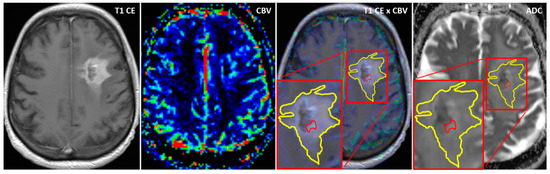

Using the MCEval ROI (region of interest) tool of the mean curve plug-in of MR neurology, two ROIs were manually placed by a neuroradiologist (authors F.E. and M.A.S.) on the image slice depicting the largest lesion diameter in the co-registered MPRAGE x DSC map: a selective ROI in the contrast-enhancing lesion area with the highest CBV value excluding vessels and nontumorous tissue, and an unselective ROI contouring the whole contrast enhancing lesion including necrotic or cystic areas. Then, both ROIs were copied onto the corresponding ADC map. A third ROI was placed in the co-registered CBV perfusion and ADC maps in the contralateral healthy white matter excluding vessels, cerebrospinal fluid, and bone. Figure 1 and Figure 2 show exemplary measurements in a patient with recurrent GBM and a patient with TRC. Image post-processing and manual ROI placement took approximately 4 min.

Figure 2. Exemplary cerebral blood volume and apparent diffusion coefficient measurements in a patient with treatment-related changes. Exemplary ADC measurement of a selective ROI (red) in the contrast-enhanced area with the highest CBV and an unselective ROI (yellow) comprising the whole contrast-enhancing lesion in a patient with treatment-related changes (TRC). After placing the ROIs carefully in the fused CBV x contrast-enhanced T1 sequence map, ROIs are copied to the exact same position in the corresponding ADC map.